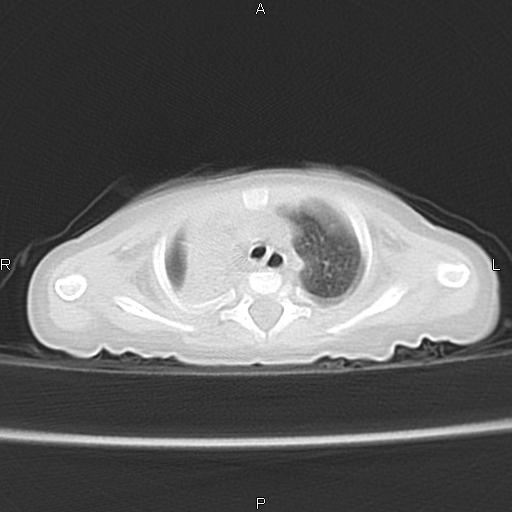

以下是引用aa13877358820在2010-7-26 12:35:00的发言:[br]男性,三个月,卧位胸片,咳嗽、气促、发热14天,两肺闻及细小水泡音。[br]